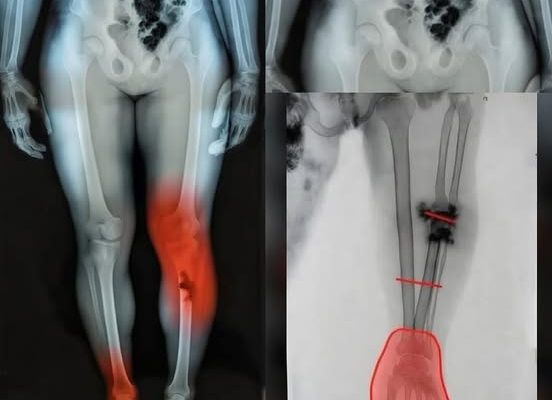

One of the most critical aspects of post-illness management is distinguishing between the expected slow pace of recovery and signs that require clinical intervention. While feeling tired is normal, certain “red flag” symptoms warrant an immediate conversation with your healthcare provider. New or unusual chest discomfort, significant shortness of breath during routine movements, or a persistent rapid heartbeat are indicators that the cardiovascular or pulmonary systems may need additional support. Similarly, unusual swelling in the lower extremities—legs, ankles, or feet—can signal a shift in fluid balance that is easily addressed when caught early. In 2026, healthcare providers emphasize that “waiting it out” is rarely the best strategy for these specific symptoms; early evaluation through simple diagnostic tools can prevent minor issues from escalating.